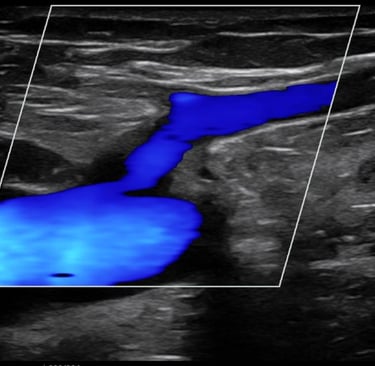

Galería

Imágenes de nuestros tratamientos en angiología y cirugía vascular.